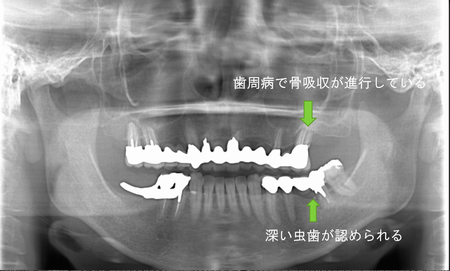

この患者様は、右上の奥歯の歯茎から出血してくるとのことで来院されました。歯周組織検査とレントゲンで診断を行った結果、重度の歯槽膿漏が認められ、保存不可能の為、抜歯になると伝えたところ、入れ歯は絶対に嫌だと言われたので、インプラント治療となりました。CT撮影を行ったところ、上顎洞底までの距離が3ミリ程度しかなかったのですが、骨が固く、フィクスチャーの一次固定が良好だったので、開窓法による上顎洞底挙上術とフィクスチャーの埋入を同時に行いました。約10カ月後に二次手術を行い、上部構造をセットしました。また、右下の臼歯部のブリッジにも大きな二次カリエスが認められ、7番の遠心根が抜歯になり、6番、7番にインプラント治療をしました。

■術前パノラマ